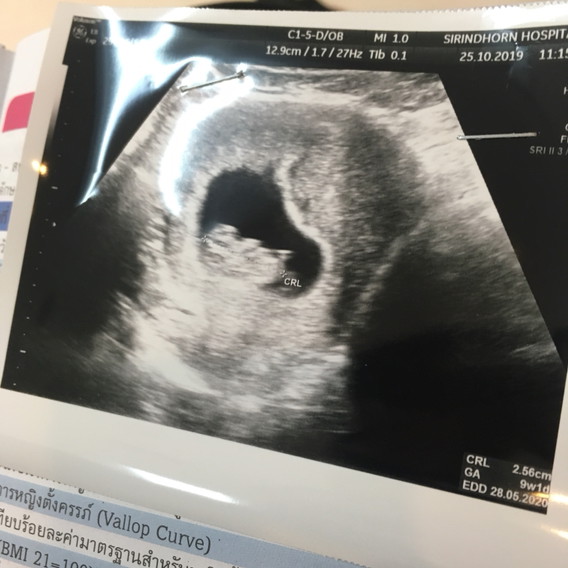

พรุ่งนี้9วีคค่ะ